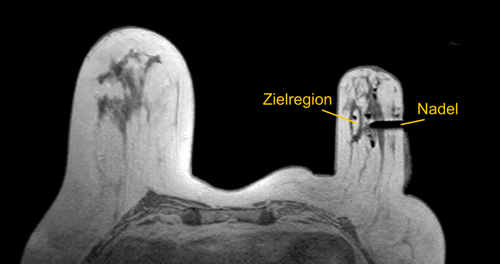

In seltenen Fällen ist die verdächtige Region nur in der MR-Mammographie eindeutig lokalisierbar. In diesem Fall wird die Probeentnahme in der Kernspintomographie durchgeführt. Diese Methode ist wegen der Begleitumstände (starkes Magnetfeld, Kontrastmittelgabe) sehr aufwändig und dauert zumeist etwa 60 Minuten.

und komprimiert, um Bewegungen während des Eingriffs zu vermeiden